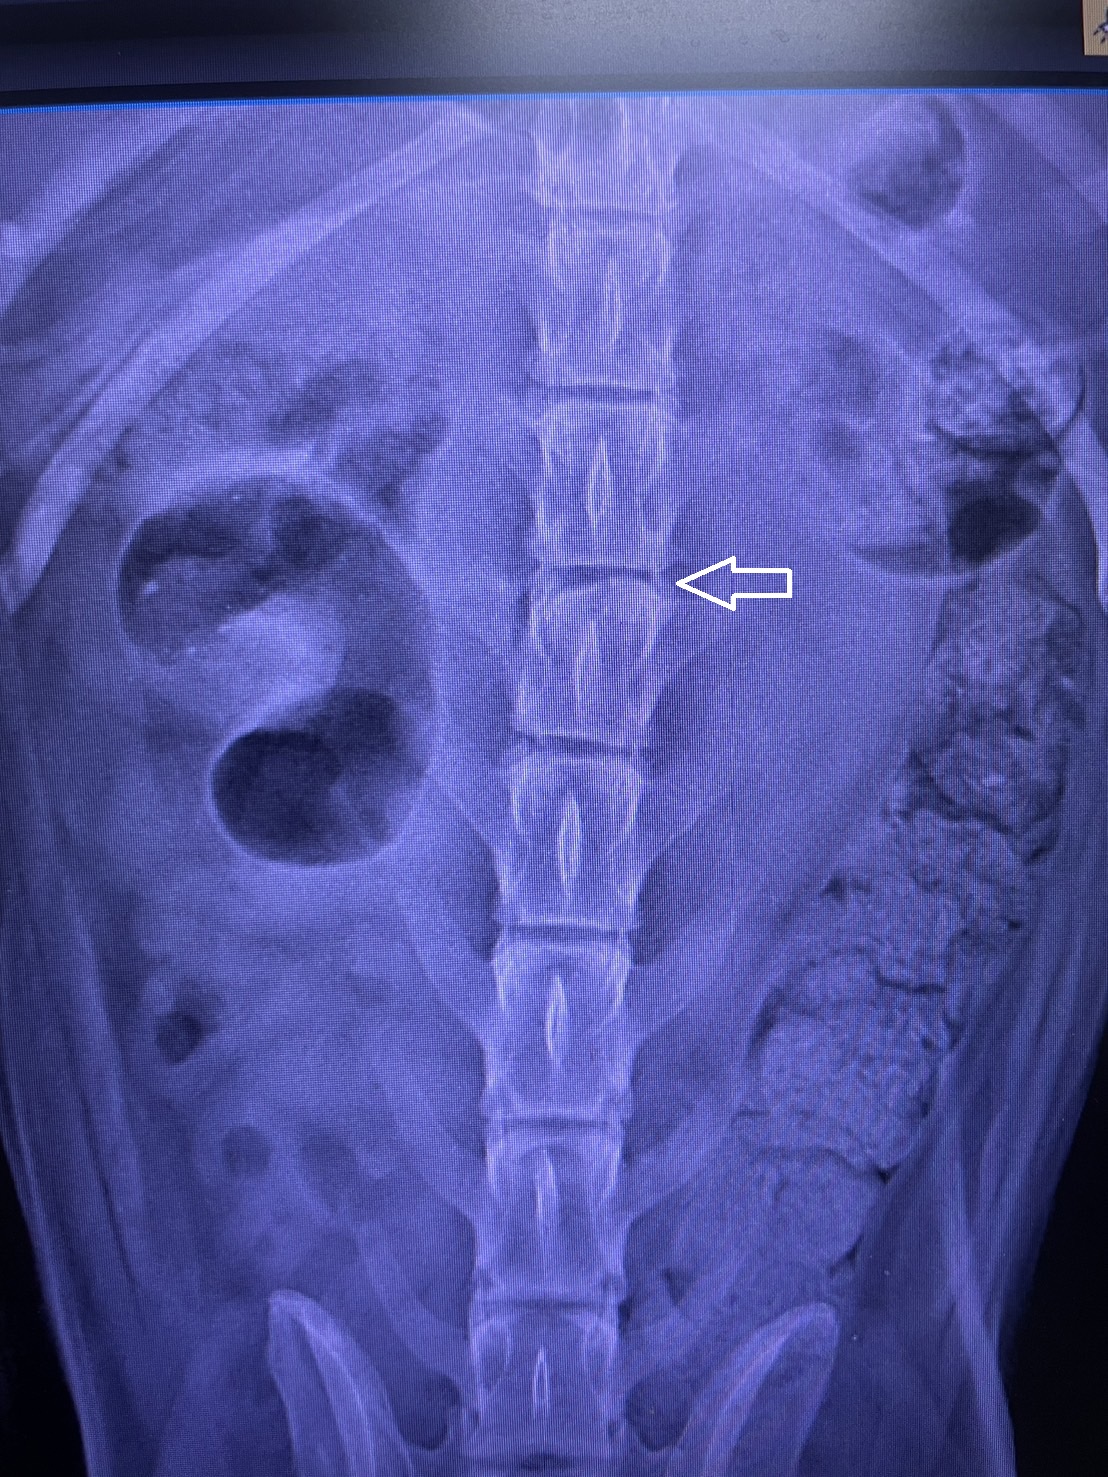

【新北市訊】新北市動保處於日前接獲通報,三峽區正義路有一隻瘦弱年老黑犬疑似癱瘓被棄置路旁。動保處立即派員將該犬帶回毛寶貝醫療中心進行檢傷及醫療。經獸醫師檢查發現,該犬體格消瘦、四肢無力且無法站立行走,X光檢查顯示脊椎狹窄,診斷為椎間盤疾病級數低於3級,並合併犬肌少症。經歷4個多月的營養調理及復健治療,這隻年老黑犬「桃樂絲」終於能正常站立、走路並能小跑步。桃樂絲符合「新北市動物之家犬貓回春雙響炮計畫」資格,領養則享有健康數據雲端管理、合作動物醫院免掛號費等多項福利,並已找到永遠溫暖的家。

板橋動物之家站長徐愛明表示,犬貓年紀增長常伴隨脊椎老化,椎間盤會失去彈性與水分,導致變形,椎間盤疾病分為5級,3級以上建議手術治療。桃樂絲入所時雖無法完整站立,但仍能自主排尿排便,椎間盤疾病約介於2至3級。除脊椎問題外,桃樂絲因營養不良導致全身肌肉量不足,表現出肌少症症狀,無法久站且四肢無力易跌倒。治療初期限制其活動以減少椎間盤損耗,經內科治療與營養補充後,桃樂絲肌肉量逐步回升。後期照護員與志工每天細心復健,桃樂絲性格乖巧,深受大家喜愛,成為團體的「團寵」。歷經努力,牠從只能勉強站立到能正常行走和小跑步,並找到溫暖的新家。